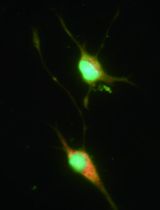

We recently published the isolation and extensive characterisation of a population of non-adherent endothelial forming cells (naEFCs) (Appleby et al., 2012) (Figure 1). These cells expressed the progenitor cell markers (CD133, CD34, CD117, CD90 and CD38) together with mature endothelial cell markers (VEGFR2, CD144 and CD31). These cells also expressed low levels of CD45 but did not express the lymphoid markers (CD3, CD4, CD8) or myeloid markers (CD11b and CD14) which distinguishes them from ‘early’ EPCs, the ‘late outgrowth EPC’ [more recently known as endothelial colony forming cells (ECFCs)] as well as mature endothelial cells (ECs). Figure 2A exemplifies the surface expression profile of the naEFCs. Functional studies demonstrated that these naEFCs (i) bound Ulex europaeus lectin (Figure 2A), (ii) demonstrated acetylated-low density lipoprotein uptake, (iii) increased vascular cell adhesion molecule (VCAM-1) surface expression in response to tumor necrosis factor and (iv) in co-culture with mature ECs increased the number of tubes, tubule branching and loops in a 3-dimensional in vitro matrix. More importantly, naEFCs placed in vivo generated new lumen containing vasculature lined by CD144 expressing human ECs and have contributed to various advances in scientific knowledge (Appleby et al., 2012; Barrett et al., 2011; Moldenhauer et al., 2015; Parham et al., 2015). Here, we describe the isolation and enrichment of a non-adherent CD133+ endothelial forming population of cells from human cord blood.

Figure 2. Surface expression phenotype of human naEFCs. A. CD133+ enriched cells at 4 days of culture were assessed for progenitor and endothelial markers by flow cytometry. Histograms show a representative experiment from ≥3 biological replicates where grey dashed lines represent isotype controls and solid black lines represent cells stained with the indicated marker. B. The function of the naEFCs was assessed by flow cytometry and compared to mature ECs, detecting the ability of cells to uptake DiI labelled acetylated low density lipoprotein (Ac-LDL) and bind FITC labelled Ulex europaeus agglutinin I (UEA-1) lectin. Density plots represent stained cells of one representative experiment from ≥3 biological replicates.